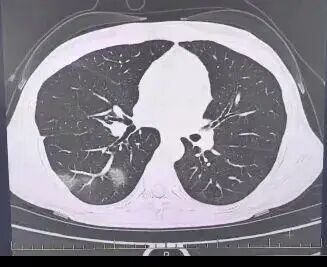

案例2:福建福州12岁女孩小婷(化名)突然发热,体温持续处在39°C~40°C的高热状态。经诊断,确诊为“甲流”,随后拿了药便回家了。第二天,家长误以为孩子病情有所好转,便没再给孩子用药。结果到了第三天,小婷再次发高烧,咳嗽不止,呼吸急促,还出现胸痛症状,甚至无法平躺。肺部CT显示:右肺出现大片实变,即“白肺”。